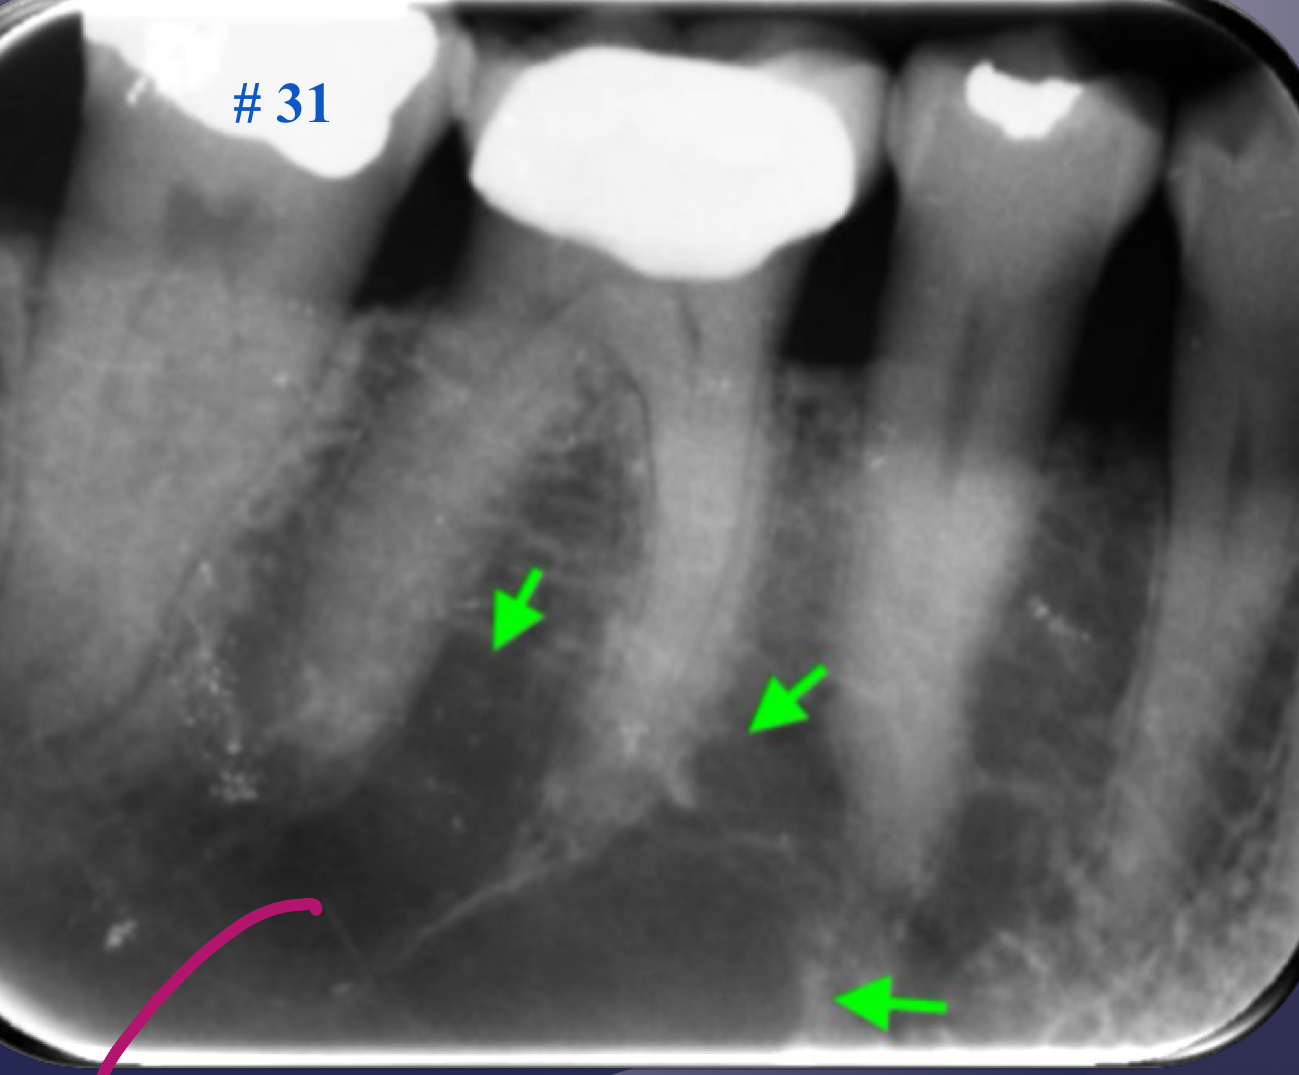

radiographic signs:

widened PDL space

loss of lamina dura

apical periodontitis

lack of continuous lamina dura, initial signÂ

early periapical lesion

widening of PDL space, thickening of LD